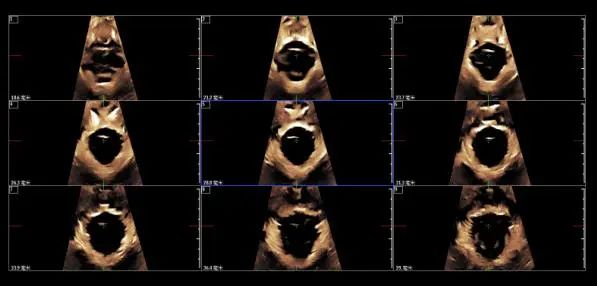

三維超聲可以獲得更加穩(wěn)定與立體的圖像,不需要移動探頭便可以完成對盆底的全面掃描,可觀察膀胱、尿道及盆底結(jié)構(gòu)的運動,同時做出形態(tài)學和功能學評價,提高了檢查的準確性。

實時三維超聲實現(xiàn)了動態(tài)立體觀察,可以提供更加準確和實時的盆底結(jié)構(gòu)觀察和盆底功能評估。

三維超聲成像可進行斷層掃描,并能對所檢查的部位進行平移和旋轉(zhuǎn)等后處理成像,能立體顯示解剖結(jié)構(gòu)與功能異常部位及相鄰組織器官的關(guān)系。